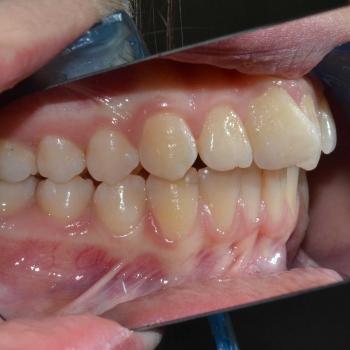

Eszter és édesanyja az iskolai fogorvosuk javaslatára kerestek fel, mert a kolléga, az esztétikai problémát okozó torlódás mellett, Angle II. osztályú funkciós eltérést is tapasztalt. Szerencsére ezeken felül egyéb eltérésre a konzultáció alkalmával sem derült fény.

Eszter a kezelés megkezdésekor headgear típusú fogszabályozó készüléket kapott annak érdekében, hogy a felső nagyőrlőket hátrafelé mozgassuk, illetve, hogy a keletkező rést felhasználjuk a kisőrlők és a szemfogak hátramozdítására is. Az így felszabadult hely az Eszter által választott hagyományos fém fogszabályozó segítségével felhasználható volt a metszőfogak elrendezéséhez, azok túlzott előredőlése nélkül.

A kezelés eredményeként minden kiindulási problémát sikerült megoldani és egy esztétikailag és funkcionálisan is szép mosolyt létrehoznunk.